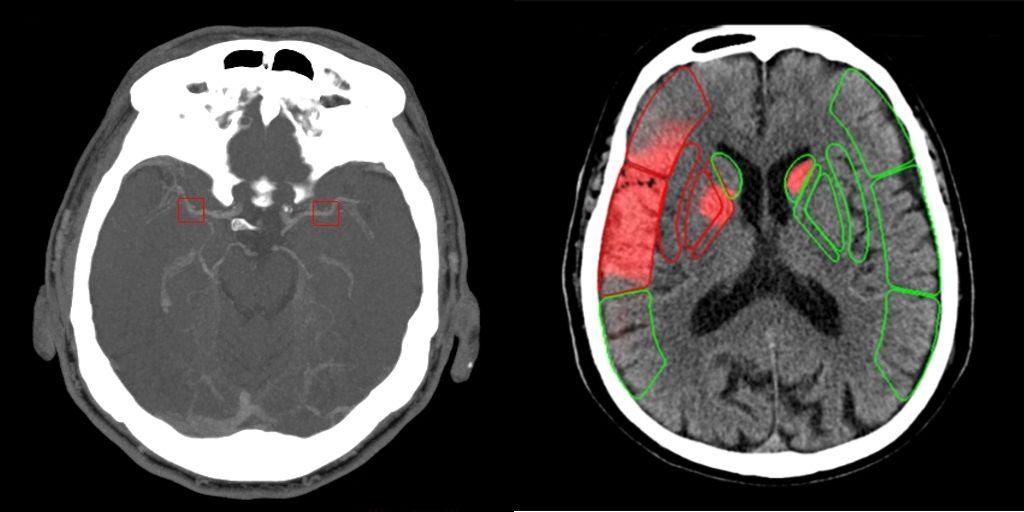

Stroke from Canon Medical integrates a comprehensive set of stroke applications including: Non-contrast CT Intracranial Haemorrhage that helps quickly locate multiple variations of intracranial haemorrhage when time is critical; Non-contrast CT ASPECTS delivering scoring of early ischemic stroke signs that are routinely challenging to detect; CT Large Vessel Occlusion to help locate occlusions in cerebral infarction patients; and CT Perfusion maps created using validated Bayesian CTP+ algorithms to help indicate potential regions of penumbra and infarct core.